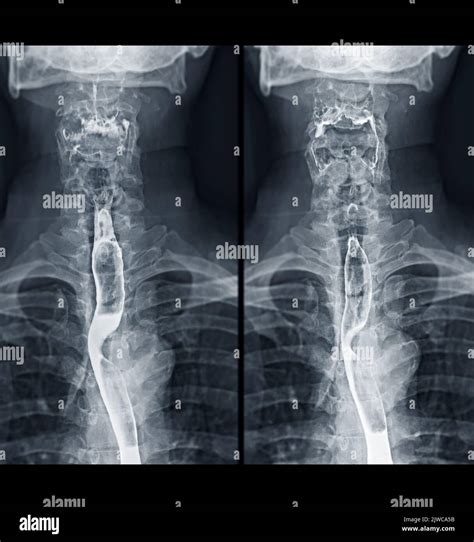

A Video Swallow Study, also known as a modified barium swallow study, is a diagnostic procedure that uses fluoroscopy to observe the swallowing process in real-time. During the study, the patient ingests barium-coated food or liquid, which makes the swallowing structures visible on X-ray images. This allows healthcare professionals to identify any abnormalities or obstructions in the swallowing pathway.

2. Barium Administration: The patient is given barium-coated food or liquid to swallow. The barium makes the swallowing structures visible on the X-ray.

3. Swallowing Observation: The healthcare provider observes the swallowing process on a monitor, noting any abnormalities or obstructions.

Interpreting the results of a Video Swallow Study involves analyzing the fluoroscopy images to identify any abnormalities in the swallowing process. Key areas of focus include:

• Oral Phase: The movement of the tongue and the coordination of the oral muscles.

• Pharyngeal Phase: The movement of the bolus (food or liquid) through the pharynx and the coordination of the pharyngeal muscles.

• Aspiration: Food or liquid entering the airway, which can lead to coughing or choking.

• Penetration: Food or liquid entering the laryngeal vestibule but not the trachea.

• Residual: Food or liquid remaining in the pharynx after swallowing.